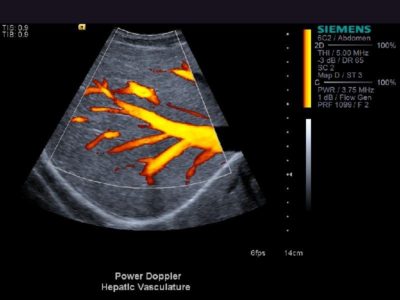

Das Prinzip der Abdomen-Sonografie ist das gleiche wie bei jeder anderen sonografischen Untersuchung. Ein Schallkopf sendet Schallwellen aus. Sie werden durch das Gewebe im Bauchraum verändert und dann vom Schallkopf wieder empfangen. Mit Hilfe eines Verstärkers lassen sich diese Wellen bearbeiten und auf einem Bildschirm darstellen.

Mithilfe der Abdomen-Sonografie können unten stehende Organe des Bauchraumes dargestellt werden. Größen- und Strukturveränderungen geben Hinweise auf bestimmte Erkrankungen, beispielsweise gut- oder bösartige Tumore oder Krebsmetastasen:

• Gefäße wie z.B. die Bauchschlagader (Aorta) und die große Hohlvene(Vena cava),

• Leber,